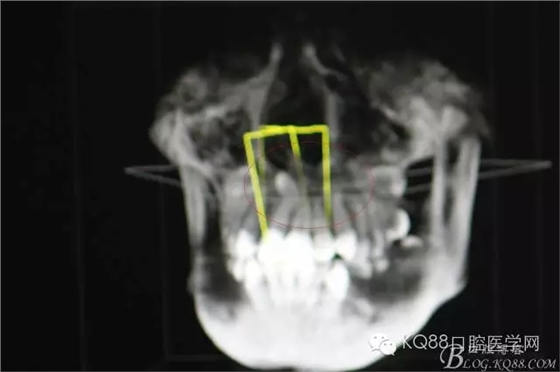

圖4.cbct的三維重建影像:多生牙牙尖幾乎和鼻底相通